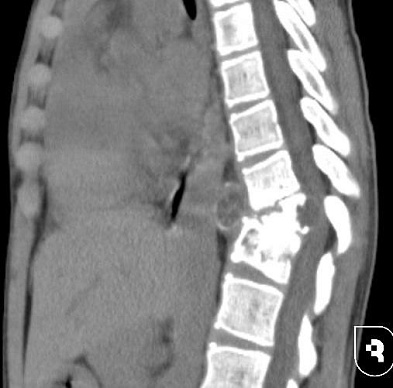

Обследование показало, что причиной симптомов стал компрессионный перелом десятого грудного позвонка, вызванный редким паразитарным заболеванием — эхинококкозом.

Во время хирургического вмешательства были обнаружены многочисленные эхинококковые кисты разного размера. Все доступные удалили, а крупные — пунктировали, чтобы избавиться от их содержимого.